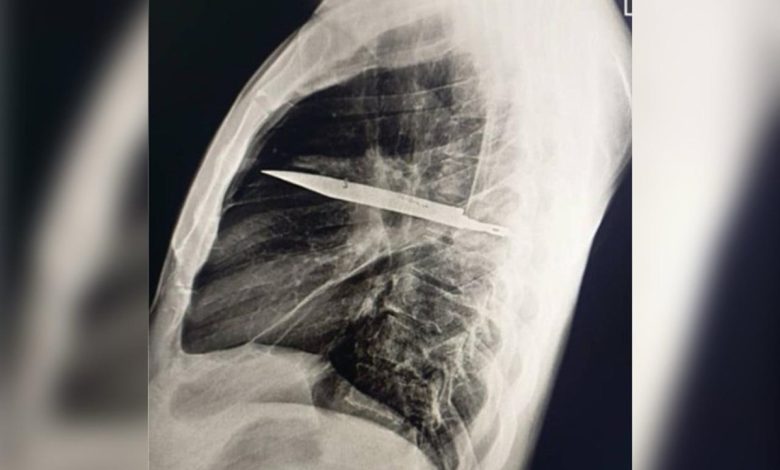

Homem descobre faca alojada no peito após oito anos sem saber

Um homem de 44 anos, na Tanzânia, fez uma descoberta chocante ao procurar atendimento médico devido a secreção com mau cheiro abaixo do mamilo direito. Após o exame, foi revelado que ele vivia com uma faca alojada no peito há oito anos, sem nunca ter percebido. O paciente relatou não sentir dores no peito, dificuldade para respirar, tosse ou febre, o que intrigou os médicos. A investigação revelou que o homem havia se machucado durante uma briga anos atrás, recebendo suturas, mas sem a realização de exames de imagem na época para verificar se algum objeto ficara no corpo. A faca estava localizada ao lado direito do tórax, próxima à escápula, sem atingir órgãos vitais, causando o acúmulo de pus e tecido danificado ao redor. Após cirurgia para remoção do objeto e drenagem do pus, o homem teve uma recuperação positiva, sem complicações adicionais. Fonte:Metropoles